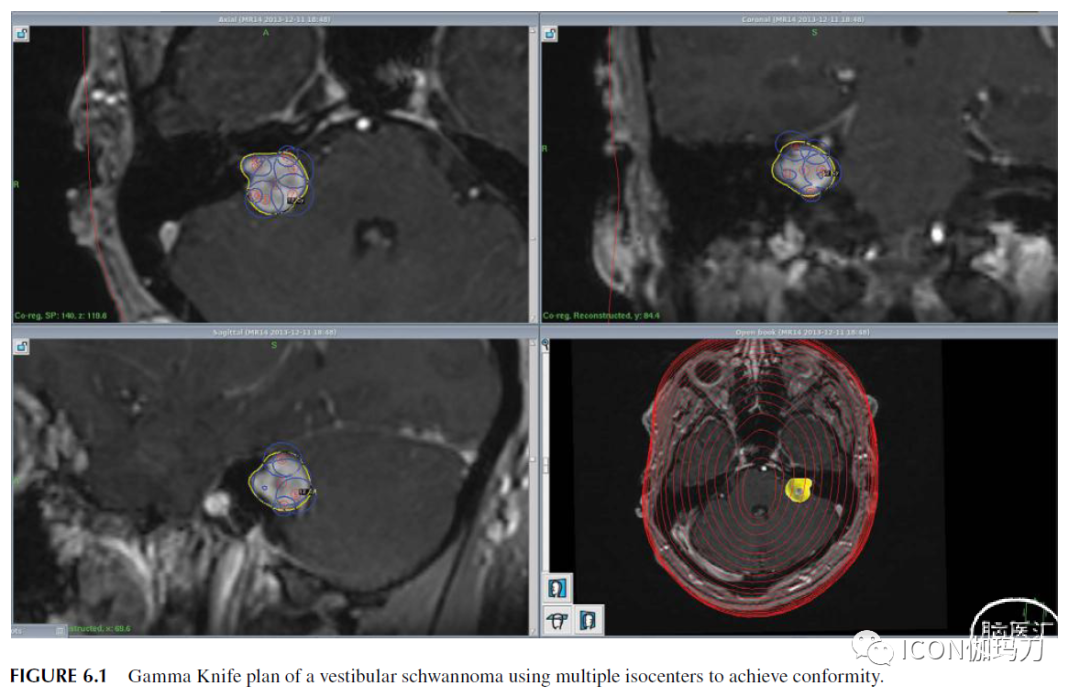

伽玛刀和其他带有锥形准直器的治疗机使用这种所谓的等中心计划技术。对于不规则形状的靶区,伽玛刀计划在靶区内部放置多个等中心,与不同的准直器尺寸相关联,以生成适形计划(Gamma Knife and other treatment machines with conical collimators use this so called isocentric planning technique. For irregularly shaped targets, Gamma Knife planning places multiple isocenters inside the target with associated different collimator sizes to generate a conformal plan)(图6.1)。这被称为球状填充(referred to as ball packing, or sphere-packing),因为许多球形电离加起来适形所期望的靶区形状(since many spherical ionizations sum to conform to the desired target shape.)。这些多个等中心创建重叠区域,本质上在所计划的靶体积内创建“热点”[These multiple isocenter create areas of overlap which essentially create “hotspots” within the planned target volume. ]。对于形状不规则的靶区,射波刀计划目的是将一些射线束对准靶区的周围区域,不经过等中心,从而将剂量补贴(patching)到这些区域。这种计划被称为“非等中心”技术(CyberKnife planning aims some beams at the peripheral region of target, not passing the isocenter, in order to patch dose to those area. Such planning is called “non-isocentric” technique)(图6.2)。

图6.1前庭神经鞘瘤的伽玛刀计划使用多个等中心以达到适形。